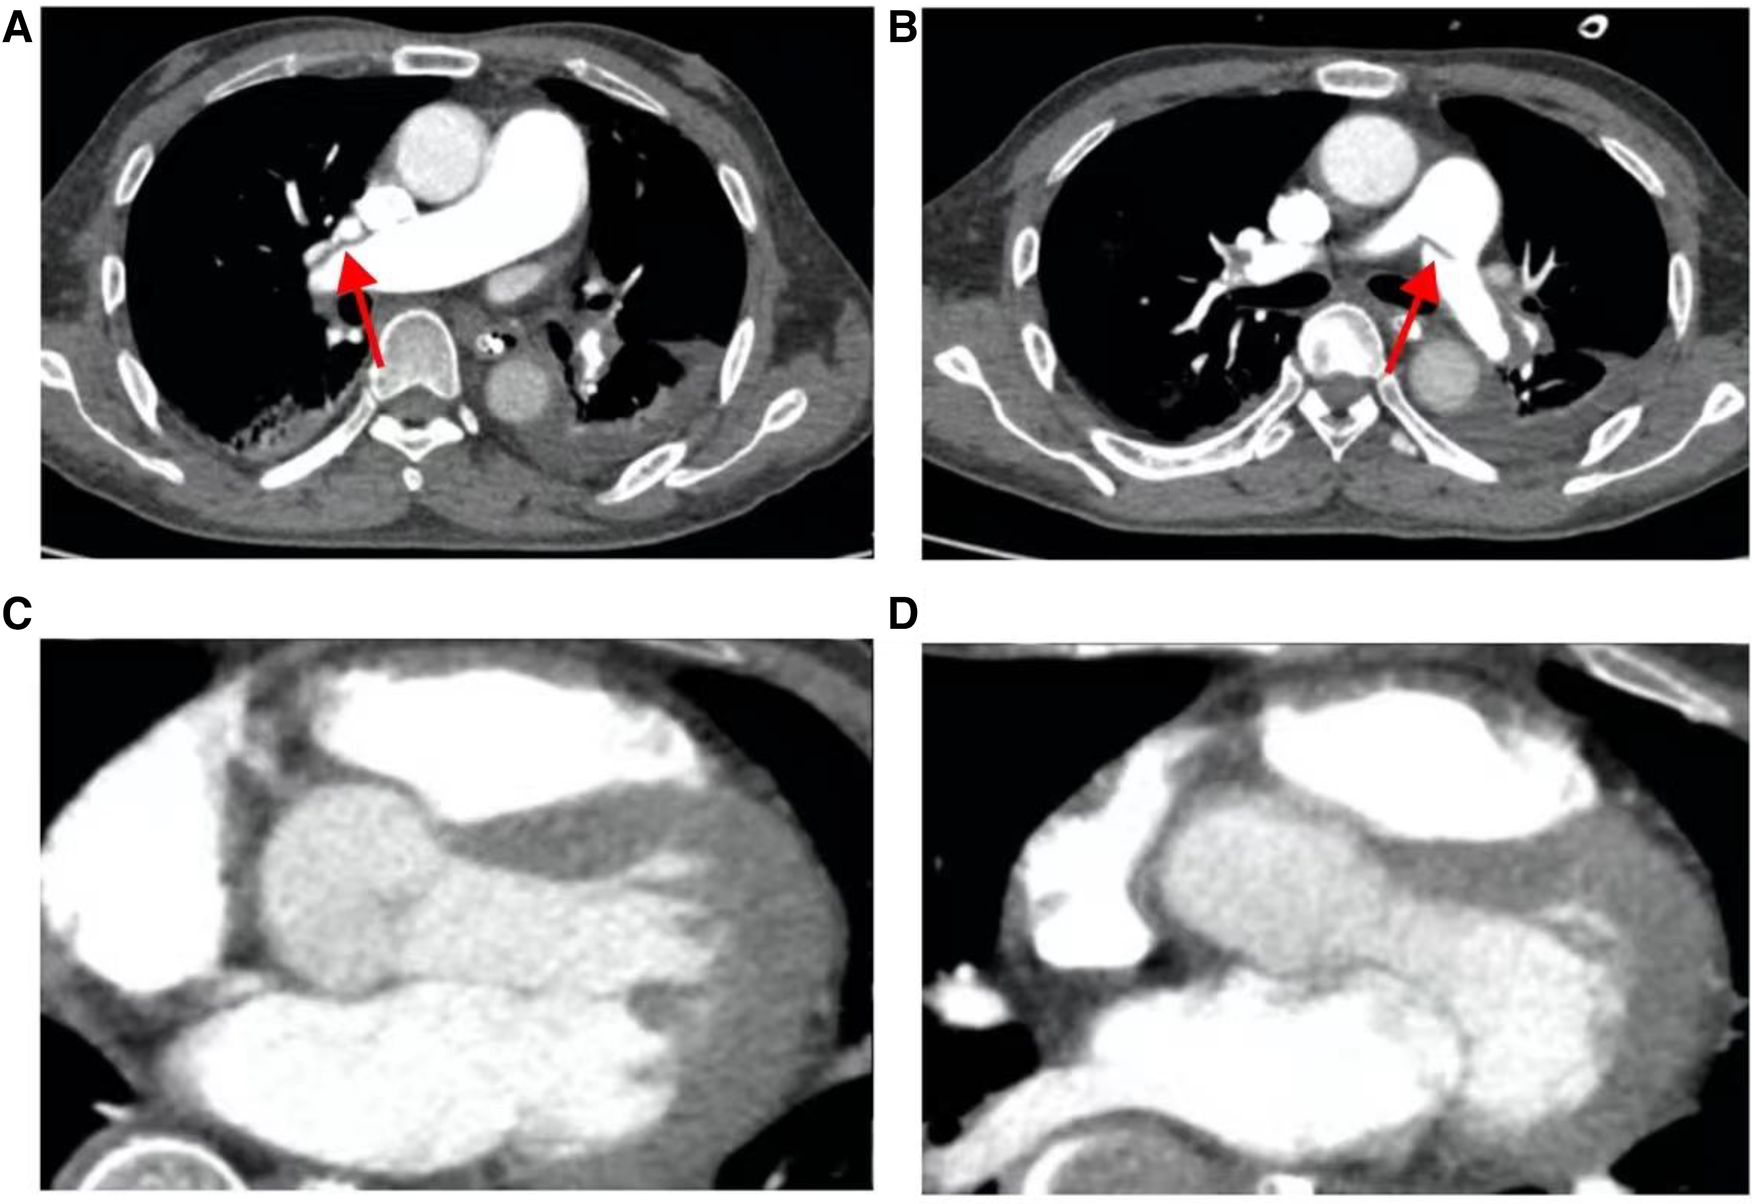

After comprehensive multidisciplinary treatment from the intensive care, cardiology, and interventional departments, the patient's indicators of infection decreased (Figure 6A), cardiac contractile function gradually improved, and his hemodynamics stabilized. Therefore, ECMO was successfully withdrawn on the fifth day post-interventional procedure. The patient's fingers showed livedo reticularis and necrosis (Figure 7A), and enoxaparin was continued. On the tenth day post-interventional procedure, the lupus anticoagulants were again positive, and CAPS was considered after consultation with the rheumatology and immunology departments. The anticoagulation treatment was then adjusted to rivaroxaban, glucocorticoids, and cyclophosphamide were added, multiple organ functions exhibited progressive improvement (Figures 6B,C). The patient was weaned off ventilator support on the 14th day post-interventional procedure. Reexamination of the pulmonary artery angiography on the 15th day indicated that the main pulmonary artery, the left and right pulmonary artery trunks, multiple lobes of both lungs, and segmental arteries showed patchy, cast-like, low-density filling defects, significantly reduced compared to before, and no abnormally thickened or twisted vascular mass was observed (Figure 8). Finally, the patient was discharged on the 20th day after interventional procedure.

Figure 8

The patient's pulmonary artery CT angiography showed less embolism on the 15th postoperative day than before. (A) Slight filling defect in the right pulmonary artery; (B) slight filling defect in the left pulmonary artery; (C, D), the chambers are now mainly patent with maybe minor wall-adherent residuals.